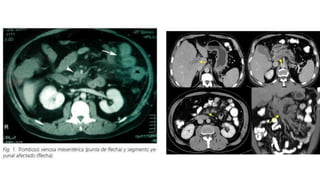

TROMBOSIS VENOSA MESENTERICA (10%)

• Agudas, subagudas y crónicas

• De origen primario cuando hay

alteraciones en la coagulación

• Secundarias si es por otros

mecanismos que predisponen a una

trombosis

DIAGNOSTICO

• TAC

• Su mayor utilidad es en el diagnostico de TVM

• Recomendación de que en Px con dolor abdominal y antecedentes de

TROMBOSIS VENOSA MESENTERICA(10%) • Agudas, subagudas y crónicas • De origen primario cuando hay alteraciones en la coagulación • Secundarias si es por otros mecanismos que predisponen a una trombosis Moya Calvo M., Acosta Gacho G., et. Al.,Patologia del mesenterio, isquemia intestinal, Medicine, 2008;10(4), pp 231-241